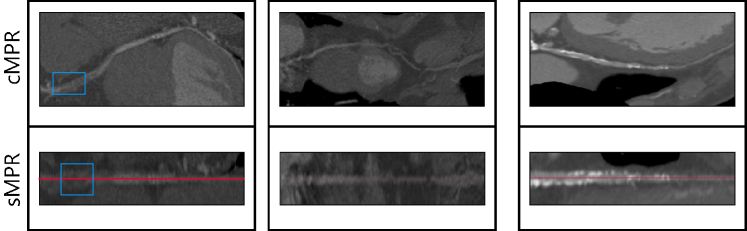

Figure 16 shows stretched multiplanar reformation (sMPR) and curved multiplanar reformation (cMPR) images reconstructed using centerlines obtained from “AuCoTrack” algorithm. These reformatted images can be directly used for the diagnosis of coronary artery disease. The proposed algorithm makes use of the local intensity information in the patches in order detect the direction to the centerlines and the bifurcation. We have shown that the model trained on CCTA images from the in-house dataset works well for the images from old Siemens scanners for CAT08 dataset.